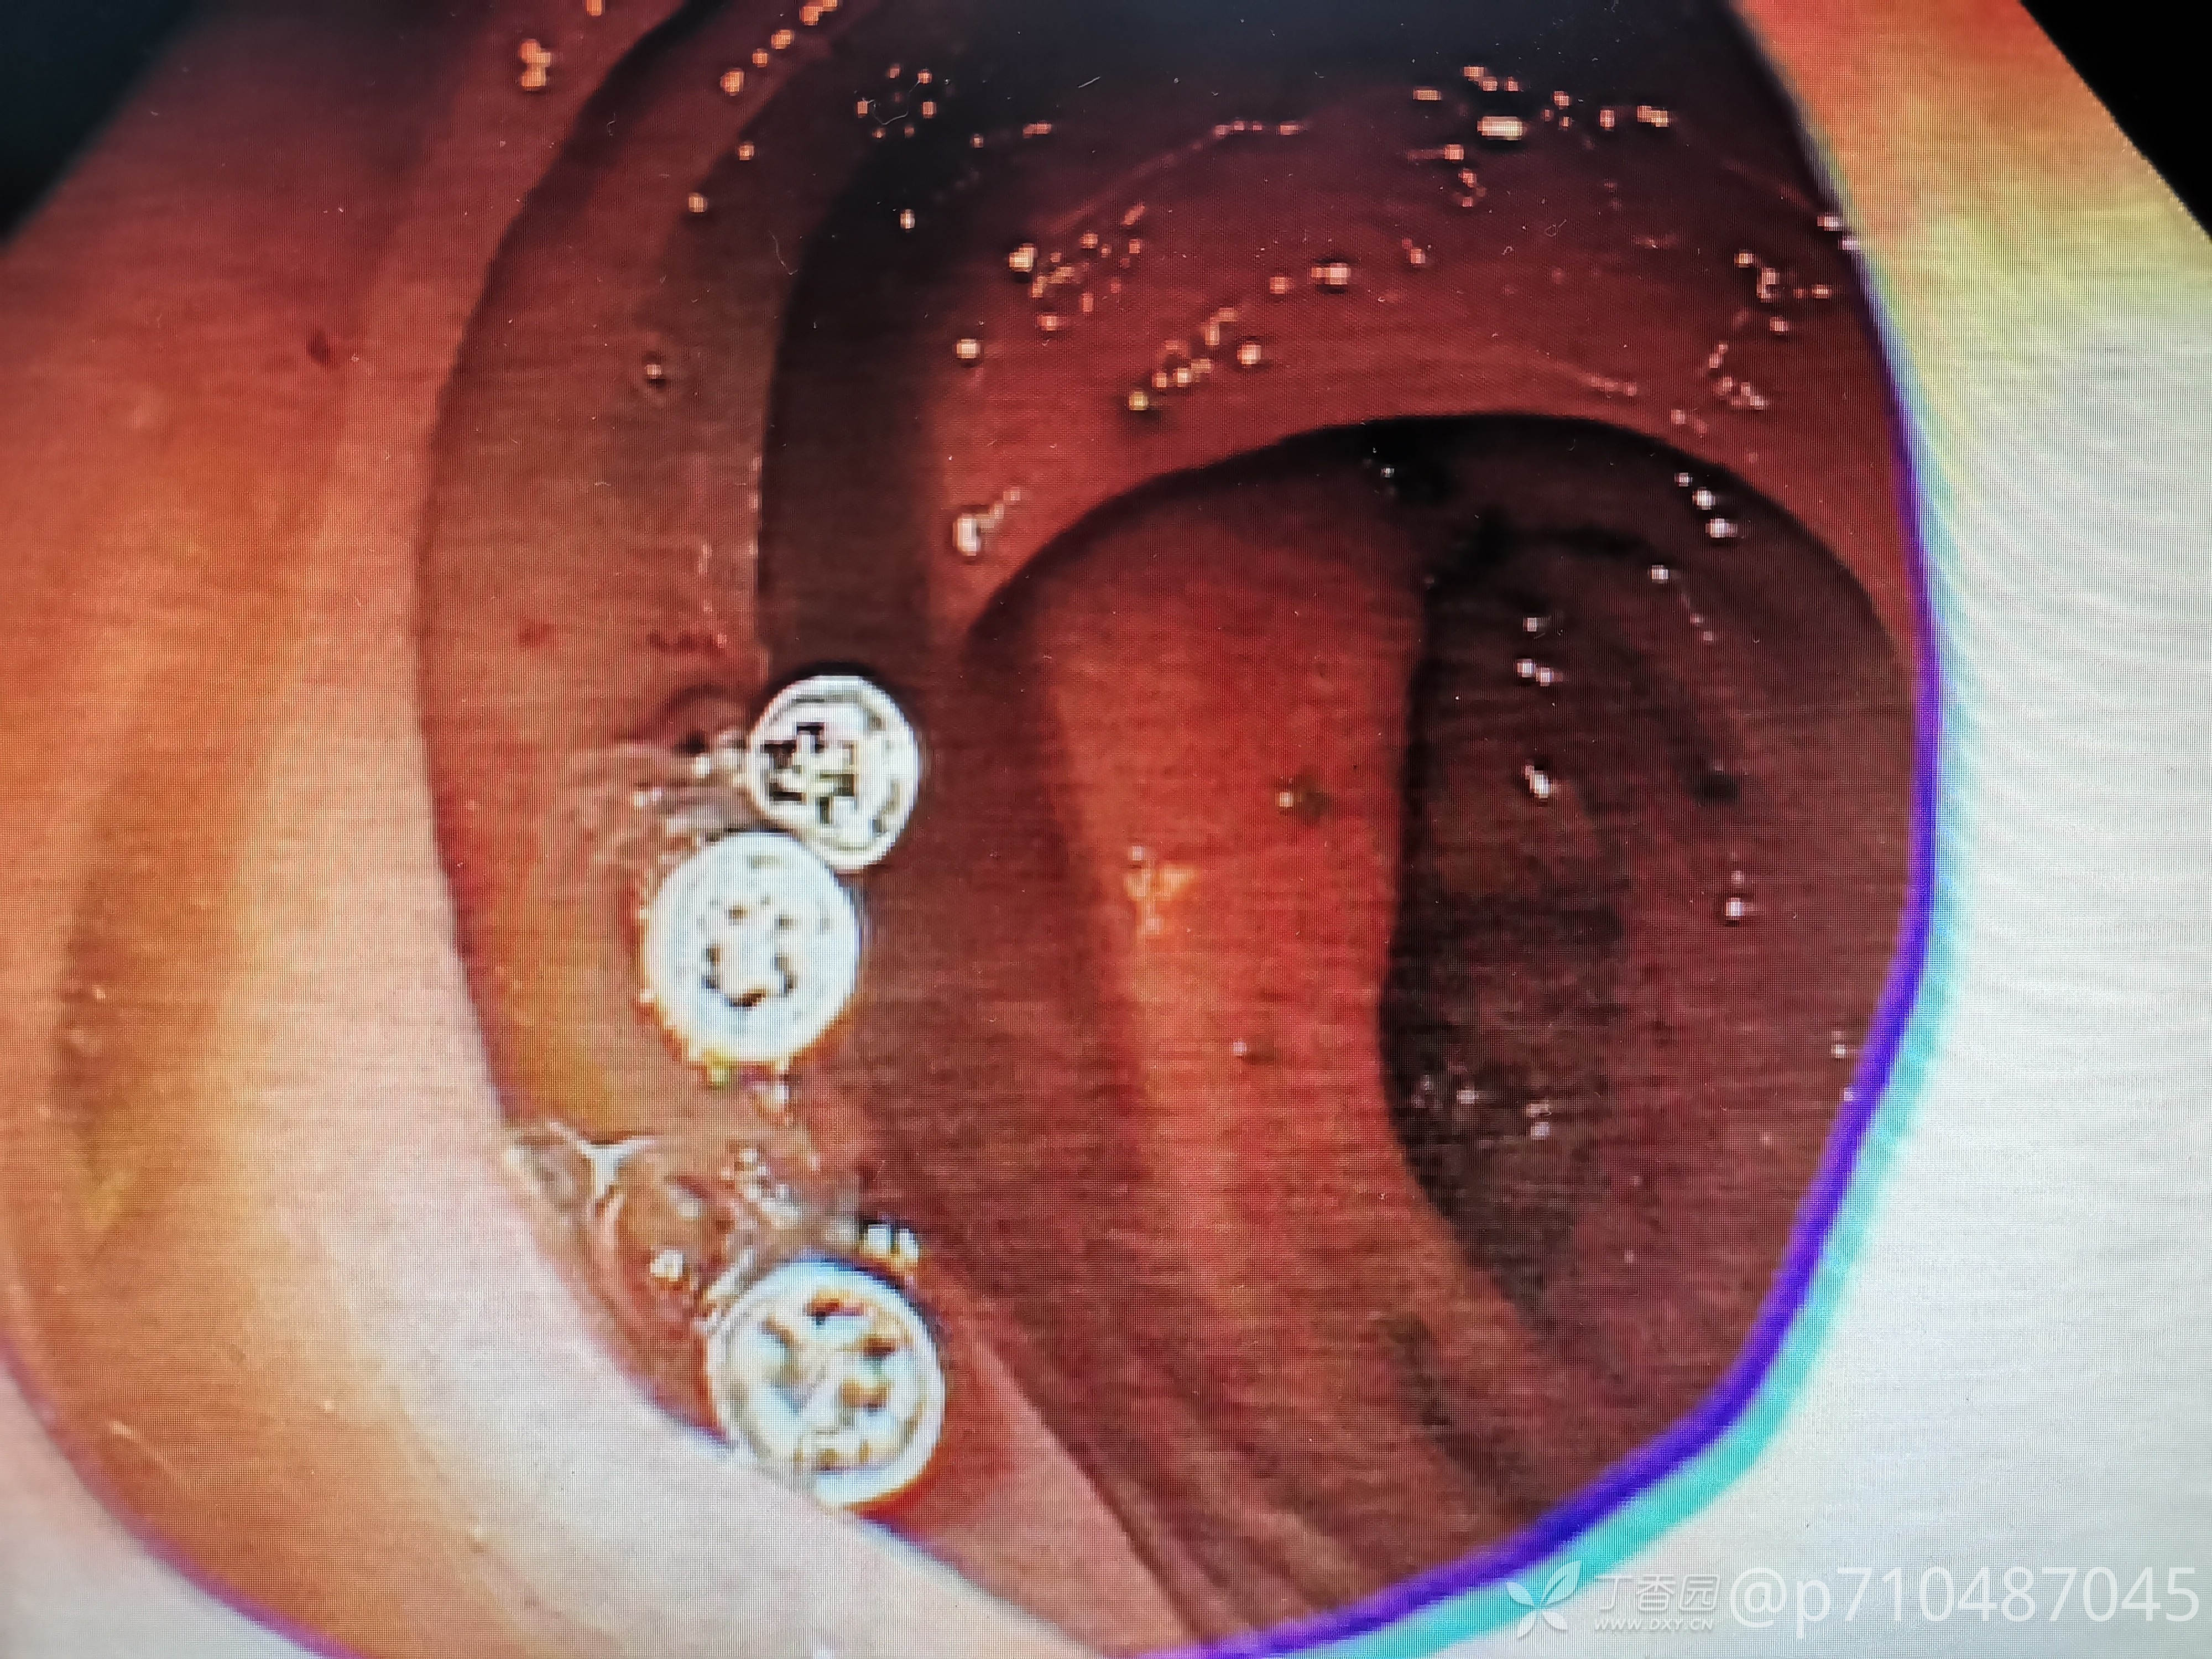

西兰花饺子 推荐第一例病人男性,50岁,第一次行肠镜检查,发现大小息肉5颗,较大者予EMR切除,这么大的第一次切,感觉可以做ESD了😂最后一个夹子打的有点松😳,来回进出几次没发现活动行出血才敢继续退镜。